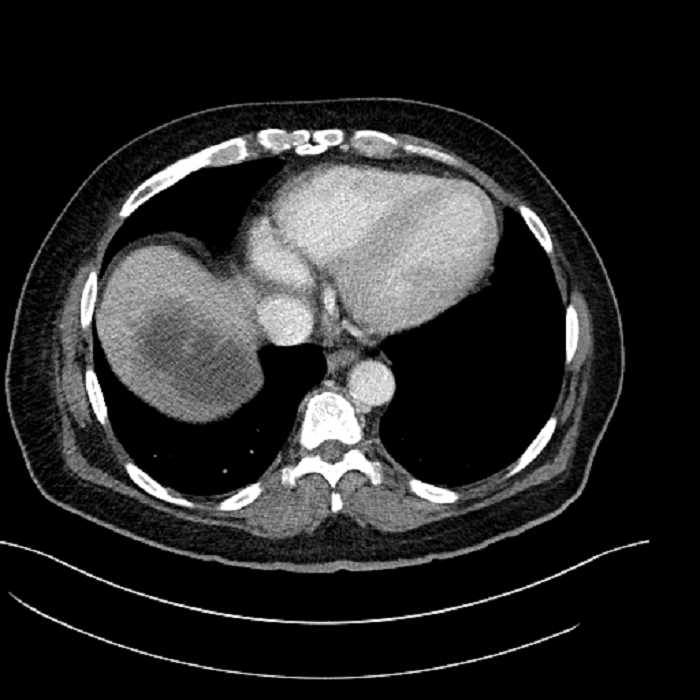

• Large fluid density structure in hepatic segments 7 and 8 measuring 10 x 7 x 7 cm with internal septation and circumferential ill-defined low density compatible with edema

• Peripherally enhancing subcapsular collections along the anterior margin of the left hepatic lobe measuring 3 x 1 cm and 2 x 1 cm

• Clearly marginated fluid density structure in segment 7 and several other scattered tiny hypodensities, which likely represent cysts

• Hepatic abscess

Acute sigmoid diverticulitis complicated by a small contained perforation and a large abscess in the right hepatic lobe. Additional small subcapsular abscesses along the anterior margin of the left hepatic lobe.

• The classic CT imaging appearance is a double target sign with internal low density surrounded by an internal enhancing rim (capsule) and a low density external rim (edema)

Hepatic abscess showing the double target sign with low density internally surrounded by a thin inner enhancing rim (red arrow) and ill-defined outer low density rim (yellow arrow). Blue arrow indicates an internal septation. Red arrows: additional smaller subcapsular abscesses. Red arrow: focal contained perforation associated with diverticulitis.